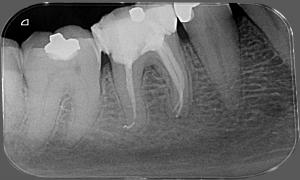

Pred zákrokom

Chrup s amalgámovými výplňami

Po zákroku

Výmena amalgámových výplní fotokompozitnými plombami s estetickým a anatomickým tvarom zubu